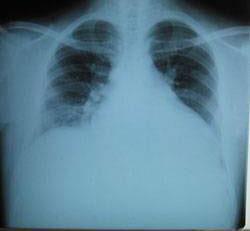

摘要:關(guān)于擴(kuò)張性心肌病的最新治療,小巷深處的隱藏寶藏正逐漸為人們所發(fā)現(xiàn)。通過(guò)先進(jìn)的醫(yī)療技術(shù)和方法,擴(kuò)張性心肌病的治療取得了新的進(jìn)展。這些治療方法旨在改善心臟功能,提高患者生活質(zhì)量。小巷深處的醫(yī)療機(jī)構(gòu)或?qū)<铱赡茈[藏著寶貴的治療經(jīng)驗(yàn)和方法,為尋求最佳治療方案的病患帶來(lái)希望。更多詳細(xì)信息需要進(jìn)一步探索和研究。

擴(kuò)張性心肌病是一種嚴(yán)重的心臟疾病,但“心之港灣”為你帶來(lái)希望,這里的專家團(tuán)隊(duì)一直在深入研究擴(kuò)張性心肌病的最新治療方法,并深知每位患者都渴望得到最佳的治療和關(guān)懷,他們努力不懈,為患者帶來(lái)生機(jī)和新生。

你將了解到最新的藥物治療、心臟康復(fù)計(jì)劃以及生活方式調(diào)整等方面的知識(shí)?!靶闹蹫场边€開(kāi)展了一系列臨床試驗(yàn),為患者提供最新的治療方案,他們的治療方法全面且個(gè)性化,因?yàn)槊總€(gè)患者的狀況都是獨(dú)特的,所以需要因人而異定制治療方案。